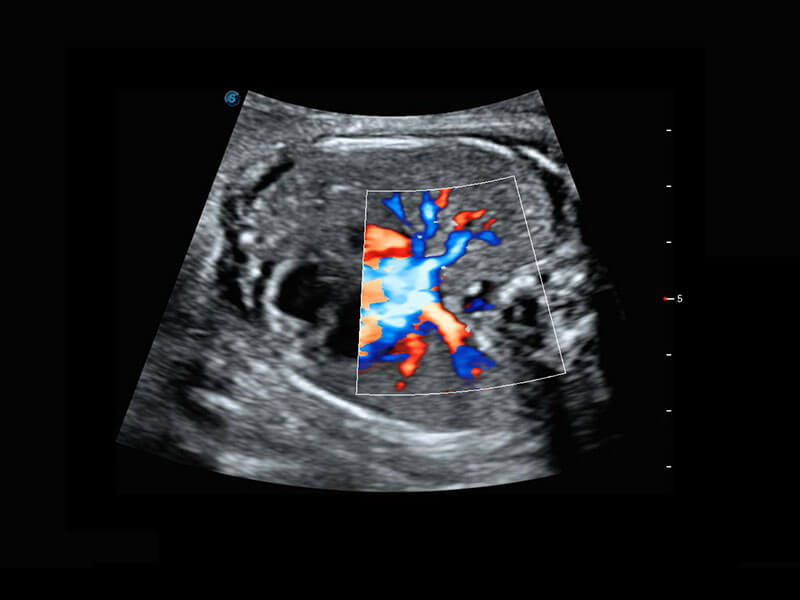

胎儿体循环

P60搭载一系列胎儿心脏成像技术,实现精细的胎儿心脏评估。

四腔切面

四腔心血流

右室双出口

胎心容积成像